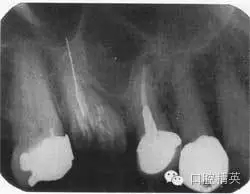

根尖片如圖44.2,可觀察到什么?

圖44.2 上頜第一磨牙的根尖片

第一磨牙大面積齲壞,已行根管充填,但只有一個(gè)牙根根管可見根尖,超充根尖接近2mm,頰根不能清楚看見,且未行充填治療,超充的根管接近于上頜竇,上頜竇向下延伸,位于第一磨牙根與第二前磨牙牙根之間,根尖無(wú)暗影。第二前磨牙已行根充治療,根充看起來(lái)剛好位于生理性根尖孔的狹窄處,但根尖有小范圍暗影。第一前磨牙冠下方可見齲壞,第二磨牙牙冠可見大范圍釘狀銀汞充填。